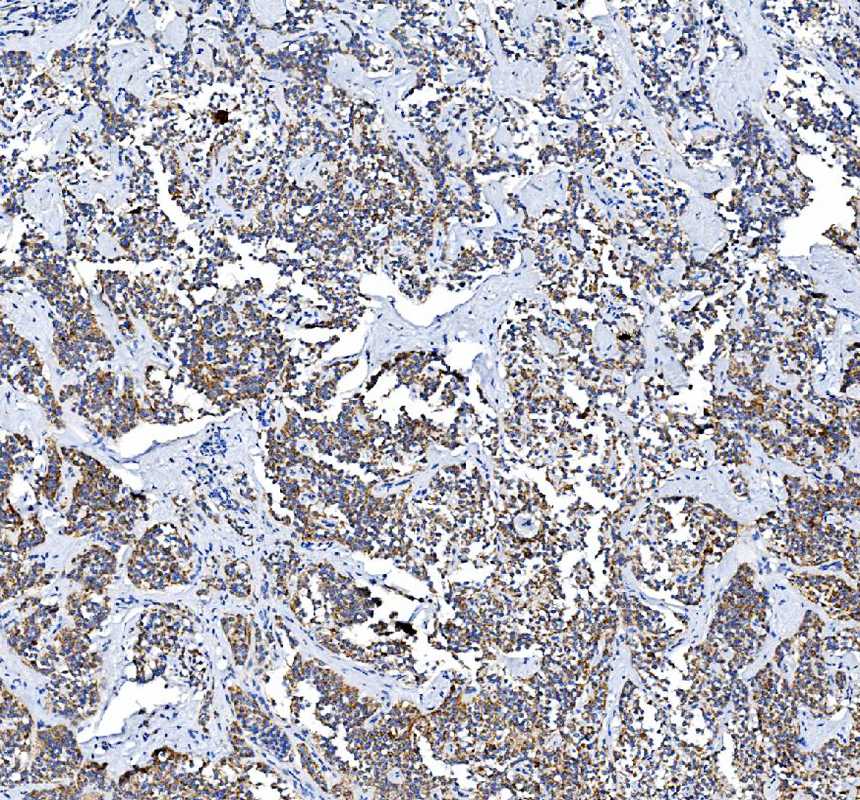

IHC analysis of PTGS2 using anti-PTGS2 antibody (A00084-2) .

PTGS2 was detected in a paraffin-embedded section of human lung cancer tissue. The tissue section was incubated with rabbit anti-PTGS2 Antibody (A00084-2) at a dilution of 1:200 and developed using HRP Conjugated Rabbit IgG Super Vision Assay Kit (Catalog # SV0002) with DAB (Catalog # AR1027) as the chromogen.